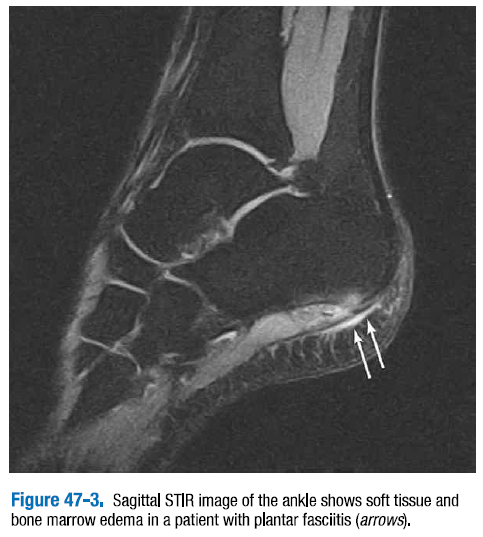

족저근막염(Plantar fasciitis)은​ 족저골극(plantar enthesophyte)을 가지거나 가지고 있지 않은 족저근막의 근위 부착부에 인접한 곳에서 증가된 T2 신호를 보인다. 근막은 두꺼워질 수 있다. 예후가 불량한 경우는 종골에서 족저근막 부착부 인접 부위의 골수종을 볼 수 있다. (그림 47-3)

△ 그림 47-3. 발목 시상면 STIR 영상. 족저근막염을 가진 환자의 연부조직과 골수종을 보여준다.